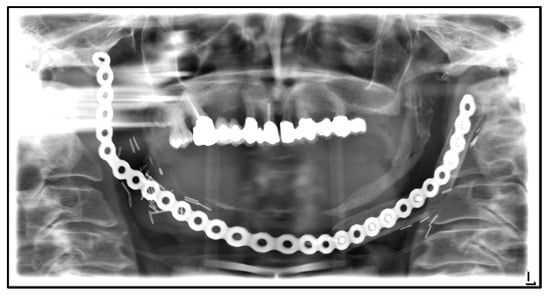

| July 2014: | Diagnosis of MRONJ in the right molar region of the mandible. Following mandibular box resection and protective plate osteosynthesis with a patient-specific plate. |

| August 2018: | Partial mandibular resection with continuity defect and alloplastic reconstruction using a patient-specific plate, excision of a submental fistula |